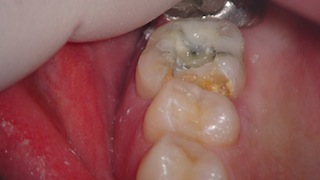

最初の状態。

ハイブリッドインレーを除去し始めたところです。

インレーの下に虫歯が残っているようにも見えます。

ハイブリッドインレー及び虫歯を除去し終わったところ。

右上の方に穴が空いているのが見えますでしょうか。

やはり露髄(神経が入っている空洞が見えてしまっている状態)が起きていました。